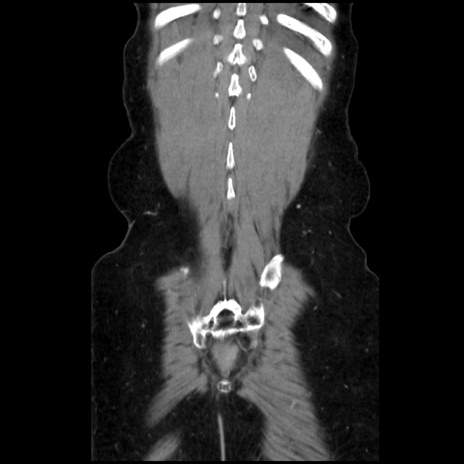

症例32(冠状断像)

矢状断像

【症例】40歳代 女性

【主訴】上腹部痛、嘔気・嘔吐

【現病歴】約9時間前頃から急に上腹部痛、嘔気、嘔吐が出現。改善しないため救急要請。

【既往歴】子宮頚癌(広汎子宮全摘術、放射線療法)、腸閉塞

【身体所見】腹部:平坦、軟、腸雑音亢進、上腹部を中心に腹部全体に圧痛あり。

【データ】WBC 8400、CRP 0.03